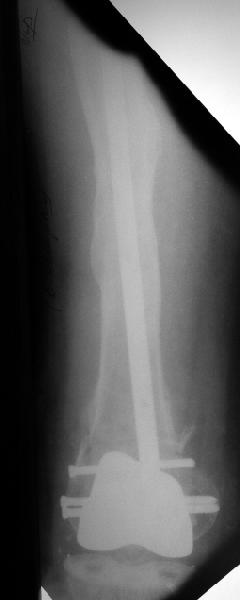

В итоге сделали антеградный остеосинтез. В дистракторе свежий перелом вправился сразу, а вот старый - оставил проблему, дистальный отлмомк остался все равно кзади. И гвоздь бы прошел кпереди от него, а ретроградный - перфорировал бы передний кортекс. Так что пришлось еще сделать чрескожную остеотомию через перелом, чтобы малость мобилизовать дистальный отломок. Снимки в прилжении.

The radiographs look excellent and a good outcome would be anticipated. The idea to osteotomize the femur shaft to compensate for the prior shaft malunion was clever and should work fine.

I can't actually see the osteotomy on either radiograph. Is it more proximal than we see in these radiographs or so well aligned as to be not visible?

The "idea" was an emergency appeared when the nail tip proceeded to the fracture level and became targeting anteriorly to the distal fragment.

The osteotomy was perfromed trough the fracture site. See the image.

Послеоперационный результат очень даже ничего.